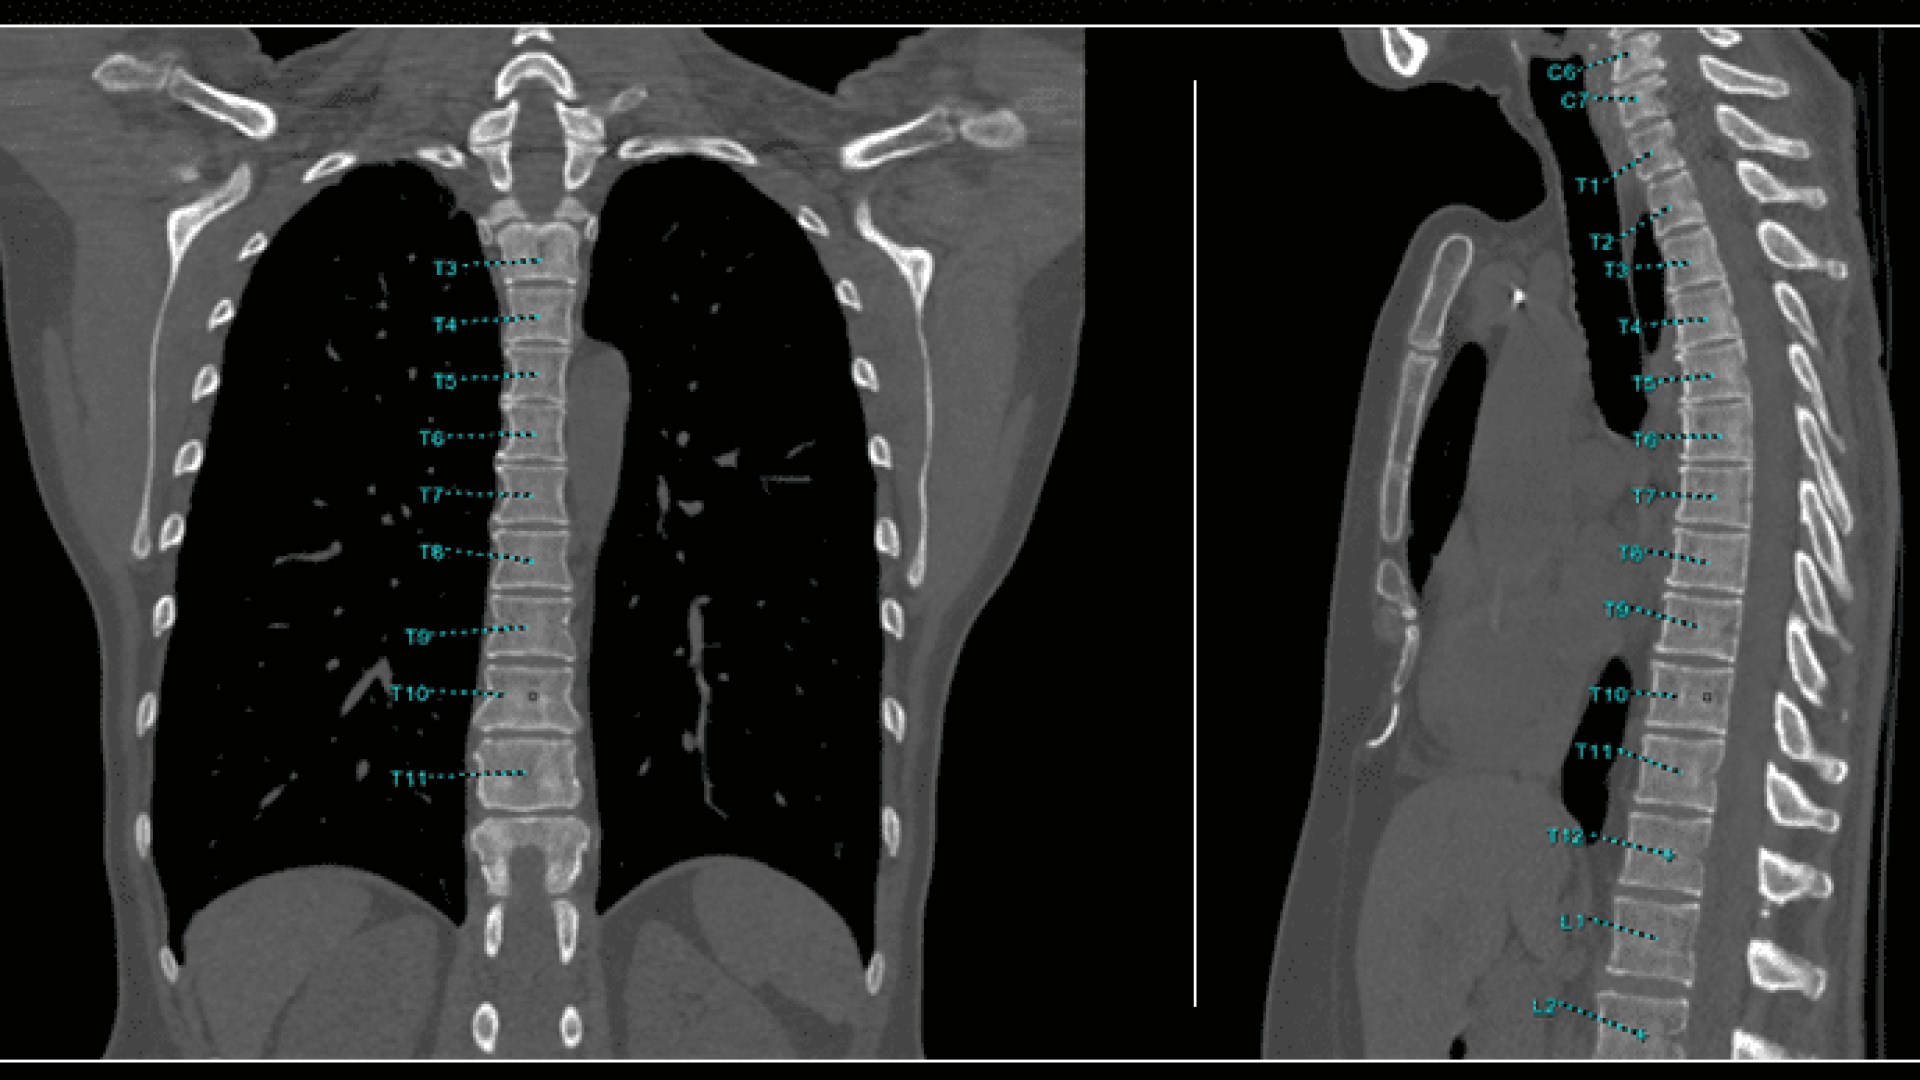

Bone VCAR

Spine assessment with deep-learning based CT application.

Automated spine identification and labelling.

>90% labeling accuracy based on Deep learning algorithm trained on global datasets acquired with a broad range of acquisition parameters.

• Automated spine labeling

• Automated generation of a 3D trace to generate oblique and straightened reformat views

• Automated generation of oblique views perpendicular to vertebral bodies and disc spaces

• Accessible for any exam type: trauma, oncology, dedicated spine, general imaging

• Works on full spine acquisitions as well as limited acquisitions containing segments of the spine